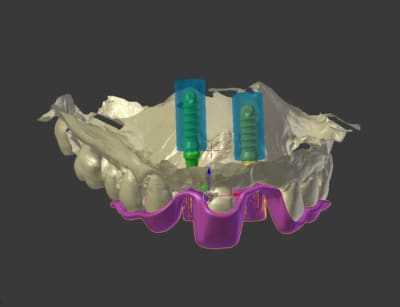

toujours avec mon nouveau jouet, je n'avais jamais testé mais cela fonctionne parfaitement bien

plus besoin de faire couler le plâtre par le labo!!!

un scan ou un cone beam de l'empreinte suffit

très simple ensuite de préparer une provisoire